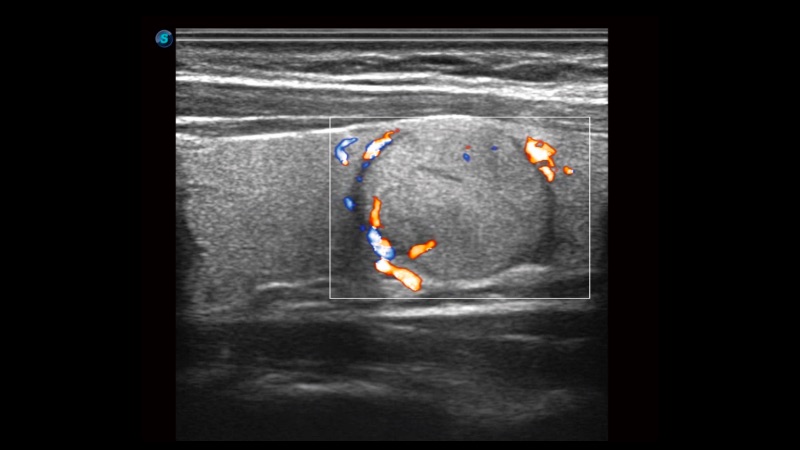

• SR Flow高分辨率血流成像技术

高分辨率血流成像技术提高了对低速血流信号的检测能力。在提高空间分辨率的同时,也克服了血流外溢现象,为用户提供更加真实的血流动力学信息。

临床图像